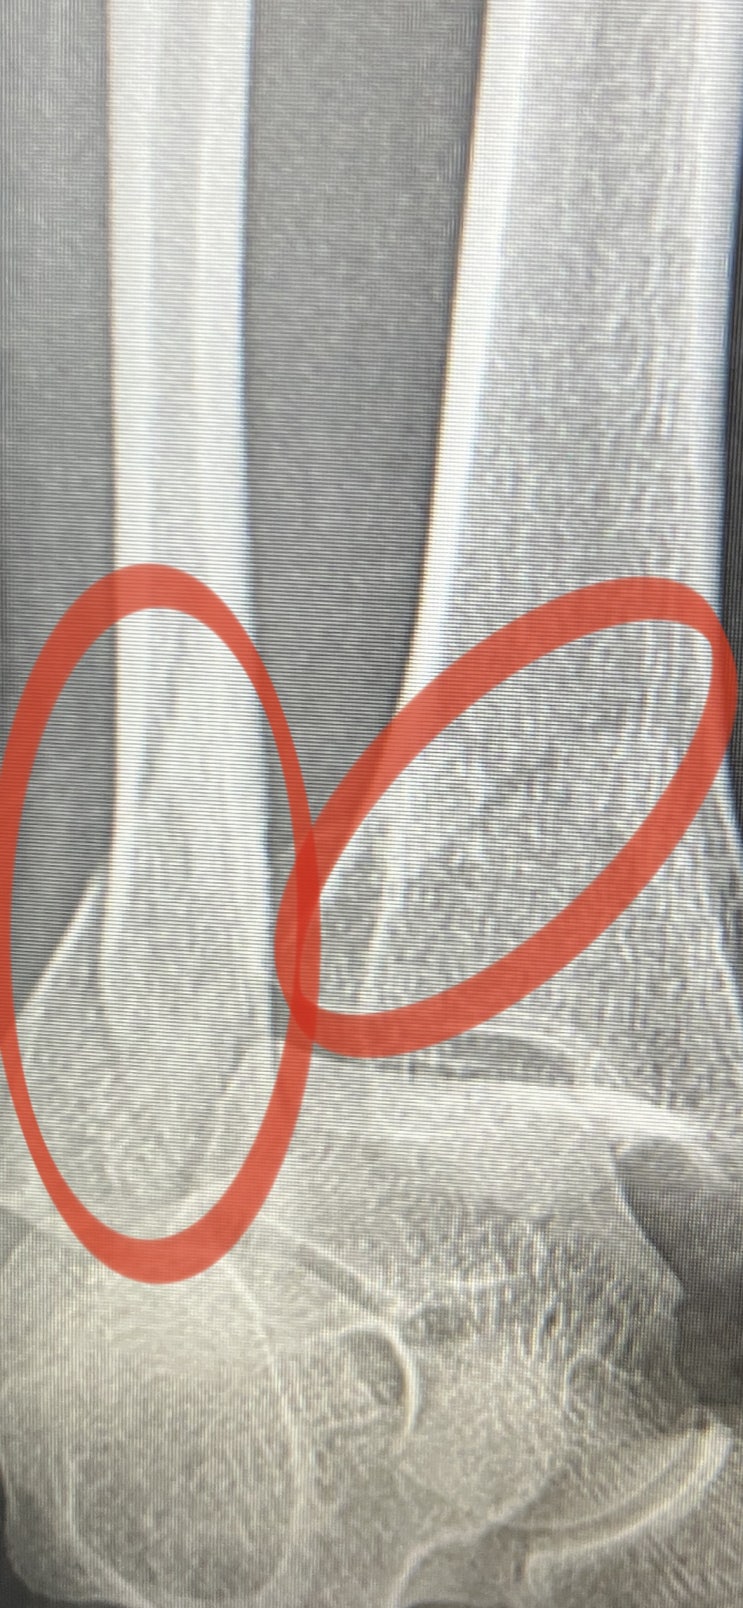

골절일기13 뼈붙는 기간 뼈 엑스레이로 골절 확인방법 외래날 주치의양반 나 탈구였어?

골절일기 벌써 13번째 골절일기? 다음일정 외래 방문 날짜 7월25일 다음 외래날짜 10월 (예약은 9월 말...